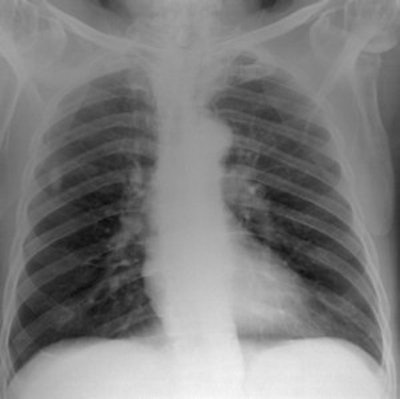

Top: Digitally reconstructed radiograph (DRR) of a chest x-ray reconstructed with a tube potential of 50 kVp. Below: DRR of a chest x-ray reconstructed with a tube potential of 150 kVp. Bottom: DRR of a chest x-ray reconstructed with an antiscatter grid. There is increased detail in the spine and diaphragm region. All images courtesy of Craig Moore.

"Although DRR resolution is not as good as real CR images, four independent expert image evaluators believe DRR images adequately simulate real radiographs and provide realistic anatomical features. Therefore, this computer model provides us with a tool that can be used by radiologists to grade quality for images derived with different x-ray system parameters, without the need to perform repeat exposures on patients," they wrote.